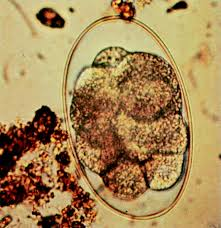

What egg is this?

Eimeria leuckarti (equine coccidia)